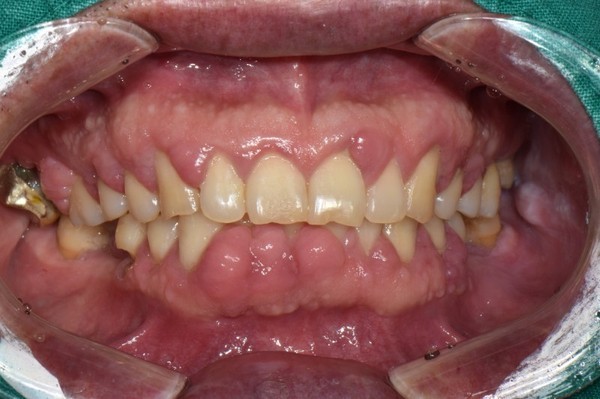

성인형 치주염은 가장 흔한 치주질환이다. 청년기에 시작되고 치료를 하지 않으면 평생 진행된다. 35세 이전까지는 임상적으로 덜 중요하다. 여성 및 남성에서 비슷하게 나타난다. 골 흡수가 천천히 진행되어 수평적인 파괴가 일어난다.

이 질환의 시모는 직접적으로 치태와 치석의 치아에 대한 부착과 관련이 있다. 치주조직의 파괴율은 질환의 활성도 및 환자의 면역에 따라 변화 할 수 있다. 그리고 성인형 지주염은 전신질환이나 숙주방어와는 무관하다.30세 이후에 매우 흔하게 나타나는 질환으로 치아가 발치될 때까지 천천히 진행된다. 성인형 치주질환의 진행은 부착소실을 일으키는 주기적 활성도를 가진다. 이 질환은 세균성 치태로 인해 생기며 국소적으로 교원섬유가 파괴된 부위에 부착소실이 일어난다. 병의 활성도는 치료나 자연적인 방어기전에 의해 숙주저항이 병의 진행을 조절할 때 감소한다. 실제로 치주염의 활성도를 측정하기는 어렵다. 가장 신뢰할만한 방법으로 치주 부착의 소실을 기록하는 방법이 있다. 이 소실은 CEJ에서부터 치주낭의 바닥까지 거리를 재는 것이다. 측정시에는 정확한 탐침기록을 요구한다.

이 병은 미국 치주학회에서 추천했듯이 병의 정도에 따라 다시 몇 가지로 나뉠 수 있는데 치과보험 및 치료계획에 매우 중요하다. 치주병의 임상증상을 통해 환자의 상태에 대한 정확한 정보를 보험 관리자에게 전달할 수 있다. 즉 성인형 지주염을 경도, 중등도, 중증 진행성으로 분류하면 더 정확한 치료계획을 세울 수 있다. 몇몇 환자는 복합된 형태를 보이는데 경도나 중등도인 환자에서 한군데 이상이 심한 부착소실을 보이는 심한 형태의 치주질환이 있을 수 있다.

2형:초기 치주염-치은염증이 더욱 심화되어 치주조직으로 파급되며 약간의 치조골 흡수가 관찰된다. 약간의 결체조직 부착소실과 치조골 소실이 나타난다.

3형:중등도 치주염-치주염의 심화된 단계 치주파괴가 더욱 진행되고 치조골 지지가 감소되기 시작한다. 치아동요도는 증가되기 시작한다. 분지부 병소가 있을 수 있다.

4형:중증 진행성 치주염-치주염이 더욱 진행되며 치조골 파괴가 심하다. 치아동요도가 심해지며 분지부 병소가 심해진다.